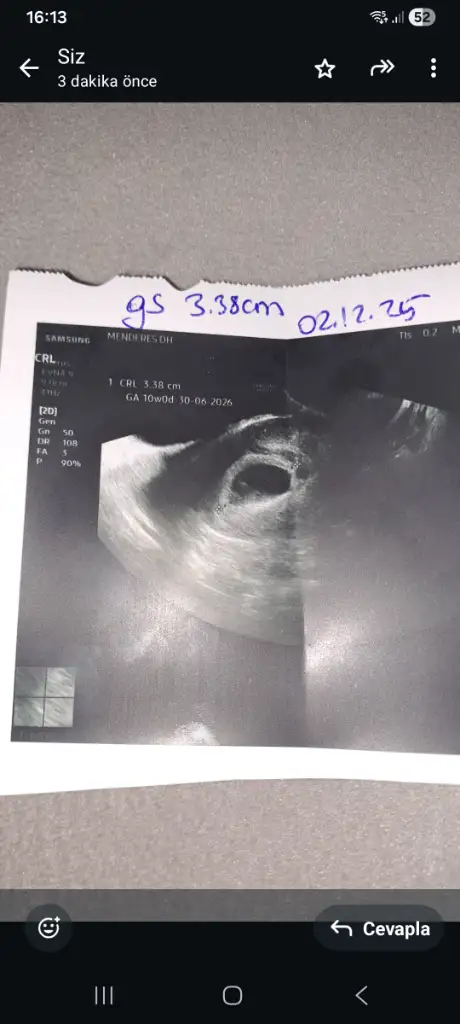

Ben yeni üye oldum. Ara ara girip takip ediyordum ama bugün doktor kontrolü de olunca artık kesinleşince üye olayım yeni arkadaşlar edineyim dedim

Bizim biraz sürpriz oldu. Hiç beklemiyorduk. Umarım hepimiz sağlıkla alırız bebeklerimizi